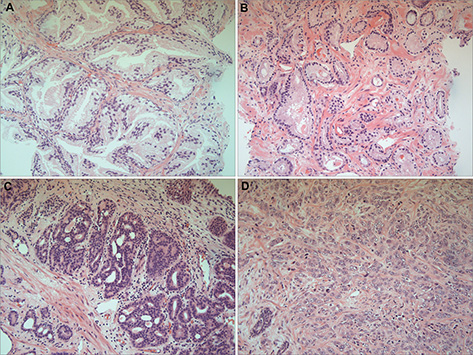

Prostate cancer involves malignancy primarily of the epithelium and is thus classed as a carcinoma. There are rarer subtypes of prostate cancer such as sarcomas (derived from mesenchyme) and lymphomas (12). Neoplastic changes normally arise in the peripheral glandular tissue of the prostate. The prostatic epithelium comprises of luminal, basal and rare neuroendocrine (NE) cell types (13). The epithelial luminal cells, expressing androgen receptors (ARs), cover the internal surface of the prostatic ducts and secrete prostatic fluid and the glycoprotein PSA. They are surrounded by basal cells, that produce proteins used for fluid production and the formation of the acinar basement membrane that separates the epithelial acini from the prostatic stroma. These cells have interspersed NE cells. Both basal and NE cell types are deficient in ARs and thus are not testosterone or androstenedione dependent (14). Fibroblasts, smooth muscle and infiltrating immunological cells combine together to form the stroma of the prostate. There is currently a large interest in identifying the cell type that is responsible for oncogenic transformation (cell of origin) in prostate cancer due to the variability of disease progression and the unpredictability of treatment response (13, 15). Prostate cancer biopsies show tissue deficient in basal cells, leading to questions as to whether there is a form of basal cell differentiation into luminal cells or that luminal cells are the primary cell of origin (13). Using these cell types, it has been hypothesized that tumors arising from luminal cells will be more aggressive than those arising from basal cells (16). About 90–95% of prostate cancers are acinar adenocarcinomas that arise from the peripheral prostatic gland (17). Histological diagnosis is made by assessing the loss of surrounding basal cells, loss of normal glandular architecture, including the disruption to the epithelial-stromal basement membrane, and nuclear atypia of luminal cells (Figure 1) (18). Aggressiveness of the adenocarcinoma is reflected in the degree of differentiation on histology. This is graded using a Gleason Score grading system, last modified in 2014 by the International Society of Urologic Pathology (ISUP) (19). This stratifies histological findings of prostate cancer with prognostic behavior, that is, the 5-year biochemical recurrence (BCR) risk following radical prostatectomy (Table 1) (20). Prostate cancer is staged using the 2018 classification for adenocarcinoma of the prostate based on primary tumor (T), lymph node involvement (N) and metastases (M). Prostate cancer typically involves regional lymph nodes in the pelvis below the bifurcation of the common iliac arteries, and metastases that are outside of the true pelvis, most commonly bone and in advanced disease, lung, and liver (21).

Fig 1

Figure 1. Prostate histology in Gleason grading groups. Gleason scoring allows physicians to predict the prognosis of patients by assessing the histological patterns of their disease. A. Normal prostate tissue showing well-formed and well demarcated glands. B. Grade Score 3 prostatic glands are well-formed and individualized meaning they are well delineated with a clear stroma. C. Gleason Score 4 glands become fused together, are poorly formed, and show a cribriform pattern. D. Gleason Score 5 there is a lack of gland formation and the presence of individual cells. This particular section also demonstrates cytoplasmic vacuoles. (Images kindly provided by Dr. Maria Bahhadi-Hardo, Consultant Histopathologist, Frimley Park Hospital, Frimley Surrey, UK).